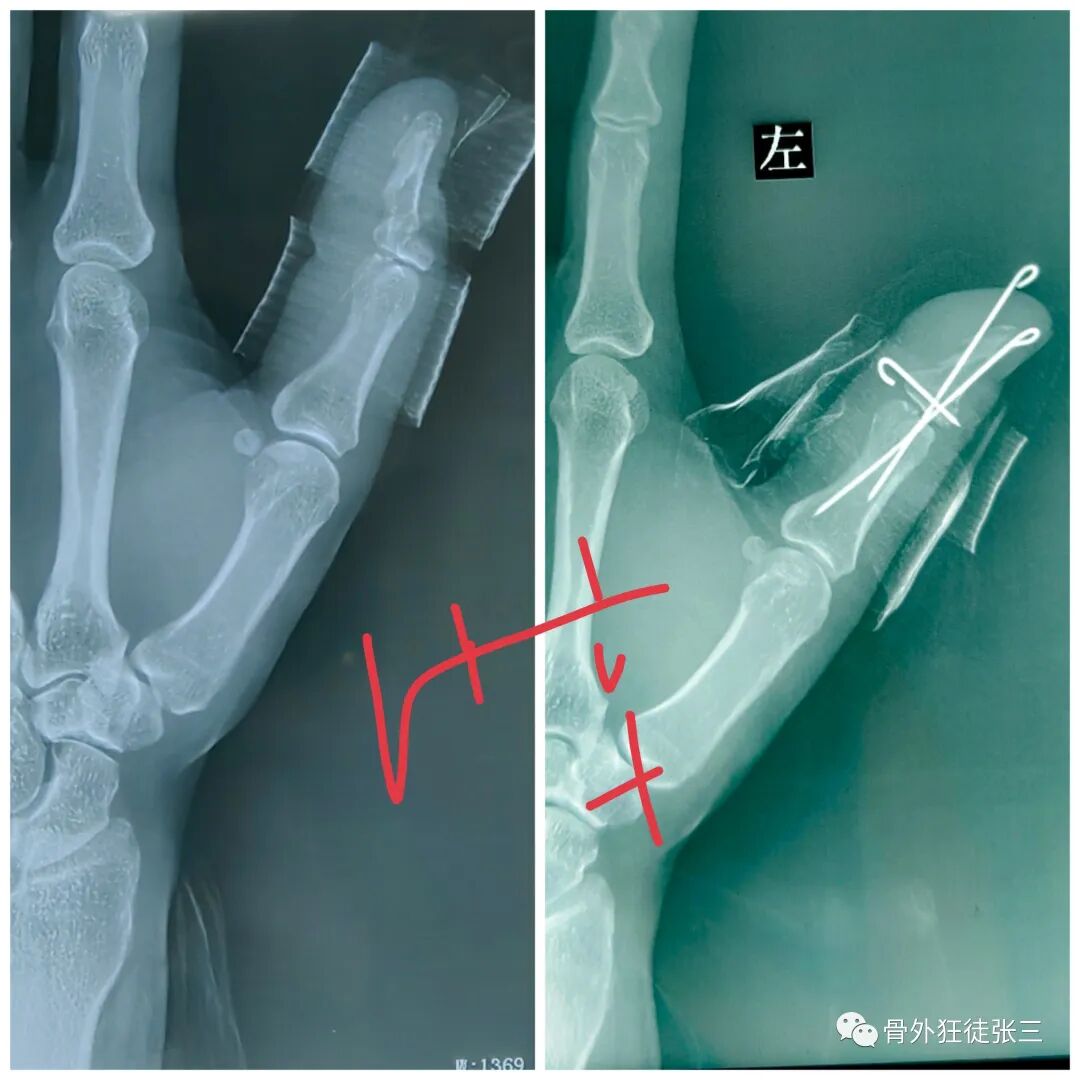

病例1,第5掌骨基底骨折,闭合复位克氏针支架,无需石膏,门诊手术,术后即刻恢复正常工作。

病例2,第4掌骨螺旋型骨折,经皮撬拔,克氏针支架。

病例5,开放性第3、4掌骨骨折,隔山打牛,克氏针支架。

病例6,开放性第2345掌骨骨折,克氏针支架

病例7,开放性掌骨,指骨骨折,克氏针内固定

病例9,第4掌骨螺旋骨折,指骨骨折,闭合复位,克氏针支架。

病例12,严重开放性手外伤保肢,克氏针固定。

病例13,拳击手骨折,克氏针支架,无需石膏,不影响工作。

病例18,第一掌骨基底部骨折,闭合复位,克氏针支架

病例19,第一掌骨基底部骨折,离合复位,克氏针支架

病例20,陈旧性第5掌骨头骨折,畸形,闭合复位,克氏针支架

病例21,指骨粉碎性骨折,闭合复位克氏针

病例22,陈旧性第5掌骨骨折,畸形,闭合复位克氏针支架

病例23,严重复杂手外伤,多发骨折,克氏针固定

病例32,第345掌骨开放性骨折,克氏针髓内+克氏针支架

病例34,掌骨、指骨粉碎性骨折,闭合复位克氏针